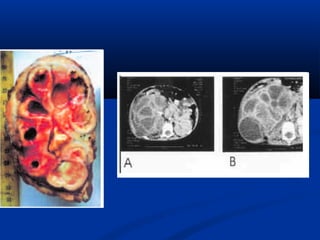

Vieâm thaän – beå thaänVieâm thaän – beå thaän

haït vaønghaït vaøng

- Beänh nhieãm truøng sinhBeänh nhieãm truøng sinh

muû maïn tính cuûa thaänmuû maïn tính cuûa thaän

laøm huûy hoaïi chuû moâ,laøm huûy hoaïi chuû moâ,

thay vaøo caùc ñaïi thöïcthay vaøo caùc ñaïi thöïc

baøo chöùa ñaày caùc haïtbaøo chöùa ñaày caùc haït

lipid.lipid.

- Thöôøng ñi keøm soûiThöôøng ñi keøm soûi

thaän vaø beänh thaän taécthaän vaø beänh thaän taéc

ngheõn.ngheõn.

 Sieâu aâm:Sieâu aâm:

• Theå lan toûa:Theå lan toûa:

• - Thaän phì ñaïi, giöõ nguyeân hình daïng, maát phaân bieät voû- Thaän phì ñaïi, giöõ nguyeân hình daïng, maát phaân bieät voû

– tuûy.– tuûy.

• - Nhieàu vuøng giaûm phaûn aâm töông öùng ñaøi thaän bò- Nhieàu vuøng giaûm phaûn aâm töông öùng ñaøi thaän bò

giaõn nôû hoaëc vuøng nhu moâ bò vieâmgiaõn nôû hoaëc vuøng nhu moâ bò vieâm

• - Ñoä thaáu aâm thay ñoåi theo möùc ñoä hoaù loûng cuûa caùc- Ñoä thaáu aâm thay ñoåi theo möùc ñoä hoaù loûng cuûa caùc

khoái nhu moâ.khoái nhu moâ.

• - Xoang thaän trung taâm coù theå taêng phaûn aâm roõ reät- Xoang thaän trung taâm coù theå taêng phaûn aâm roõ reät

keøm boùng löng töông öùng vôùi soûi san hoâ lôùn.keøm boùng löng töông öùng vôùi soûi san hoâ lôùn.